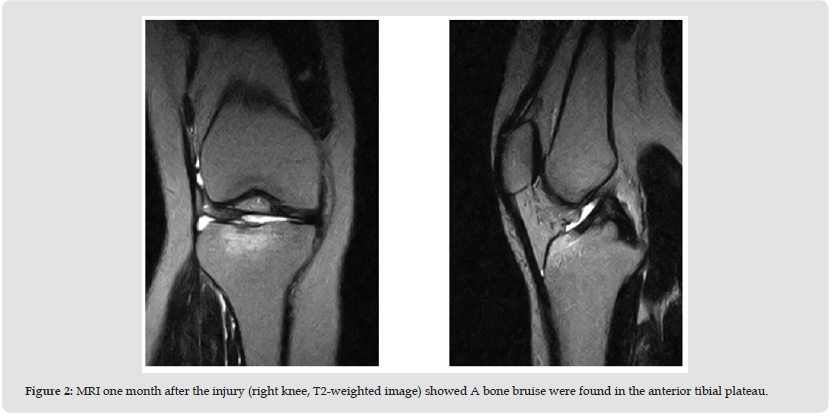

A 28-year-old female presented with severe right knee pain and gait disturbance. The symptoms began after a dog bumped her. She nearly fell, stepped forward with her right foot to brace herself, during which her knee gave way. She was taken to a nearby hospital where MRI revealed no significant findings (Figure 1). She returned to work, but her knee pain gradually worsened. One month later, a repeat MRI showed a bone bruise in the anterior tibial plateau (Figure 2). Her symptoms persisted for approximately 2 months. Therefore, prompting referral to our department. Her past medical and family histories were unremarkable. Physical examination revealed no swelling, or effusion, but tenderness was noted in the right knee. The range of motion was 0°-145°. McMurray test for meniscal injury were negative. The anterior and posterior drawer tests, as well as varus and valgus stress tests, were normal. The Lachman test was positive. The patient had no patellofemoral symptoms. Her Lysholm knee score was 42. Plane radiographs showed no bony or soft tissue abnormalities, including intra-articular loose bodies. Computed tomography revealed no subchondral bone loss (Figure 3). MRI confirmed the presence of a bone bruise in the anterior tibial plateau.

In this case, MRI at the time of injury revealed no bone bruises. However, 1 month later, when the patient’s pain had worsened, bone bruise appeared on MRI. Moreover, as the pain subsided, the bone bruise also resolved. Traumatic bone bruises typically result from direct injury that disrupts the trabeculae of subcortical bone, leading to the accumulation of interstitial fluid and hemorrhage within the extracellular space [4]. On MRI, bone bruises are identified by subcortical hypointense signals on T1-weighted images and hyperintense signals in T2-weighted images, reflecting a localized increase in fluid content [5]. Bone bruises of the tibiofemoral joint serve as a footprint of the dynamic forces within the joint at the moment of ACL rupture, offering insights into the mechanisms of injury [6-8]. Characteristic bone bruise patterns in ACL injuries have been described, with the lateral tibial plateau (LTP) and lateral femoral condyle (LFC) being the most common sites. Notably, the posterior LTP and central LFC are most frequently affected [9-13]. Studies have reported that a higher incidence of bone bruises in the lateral compartment suggests the presence of valgus stress during the ACL injury, which may lead to opening of the medial joint space [6,14].